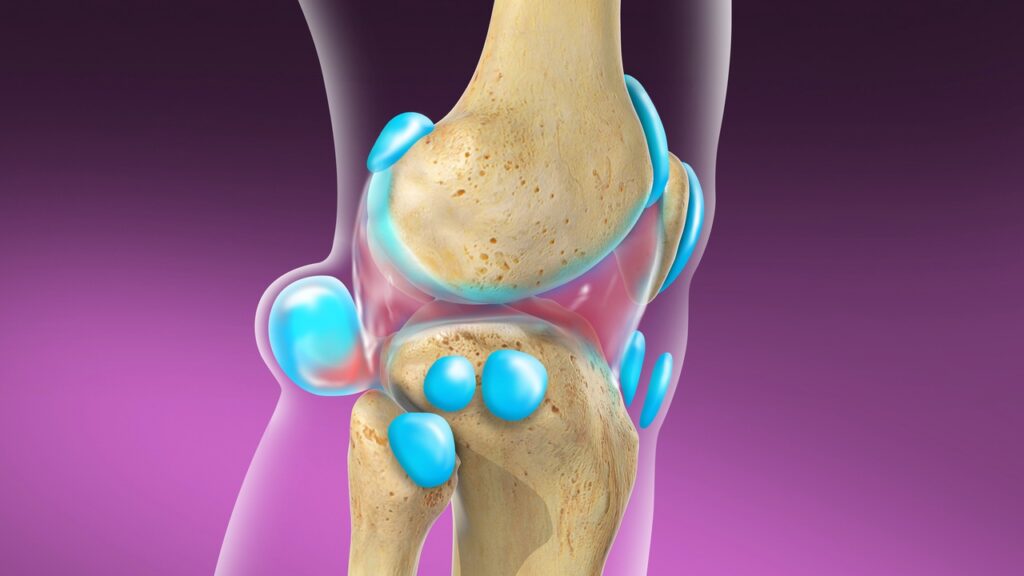

قیمت: 52٬500 تومان - دسته بندی فایل: پاورپوینتدانلود پاورپوینت آشنایی با کیست بیکر زانو

خرید پاورپوینت حرفه ای با موضوع آشنایی با کیست بیکر زانو با قیمت استثنایی از لوکس فایل